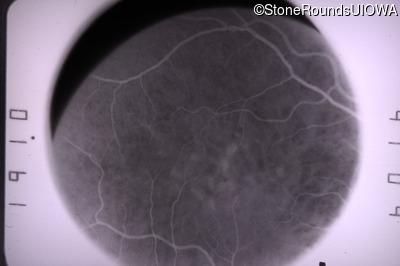

This 31 year old woman had subtle macular abnormalities discovered incidentally earlier that year. Her medical history at the time was unremarkable except for gestational diabetes during her most recent pregnancy. Five years later she was diagnosed with type 2 diabetes managed with oral medication. Two years later she developed sufficient hearing loss that hearing aids were required. Her acuity remained 20/20 OU at that time.

Age at visit: 31 years